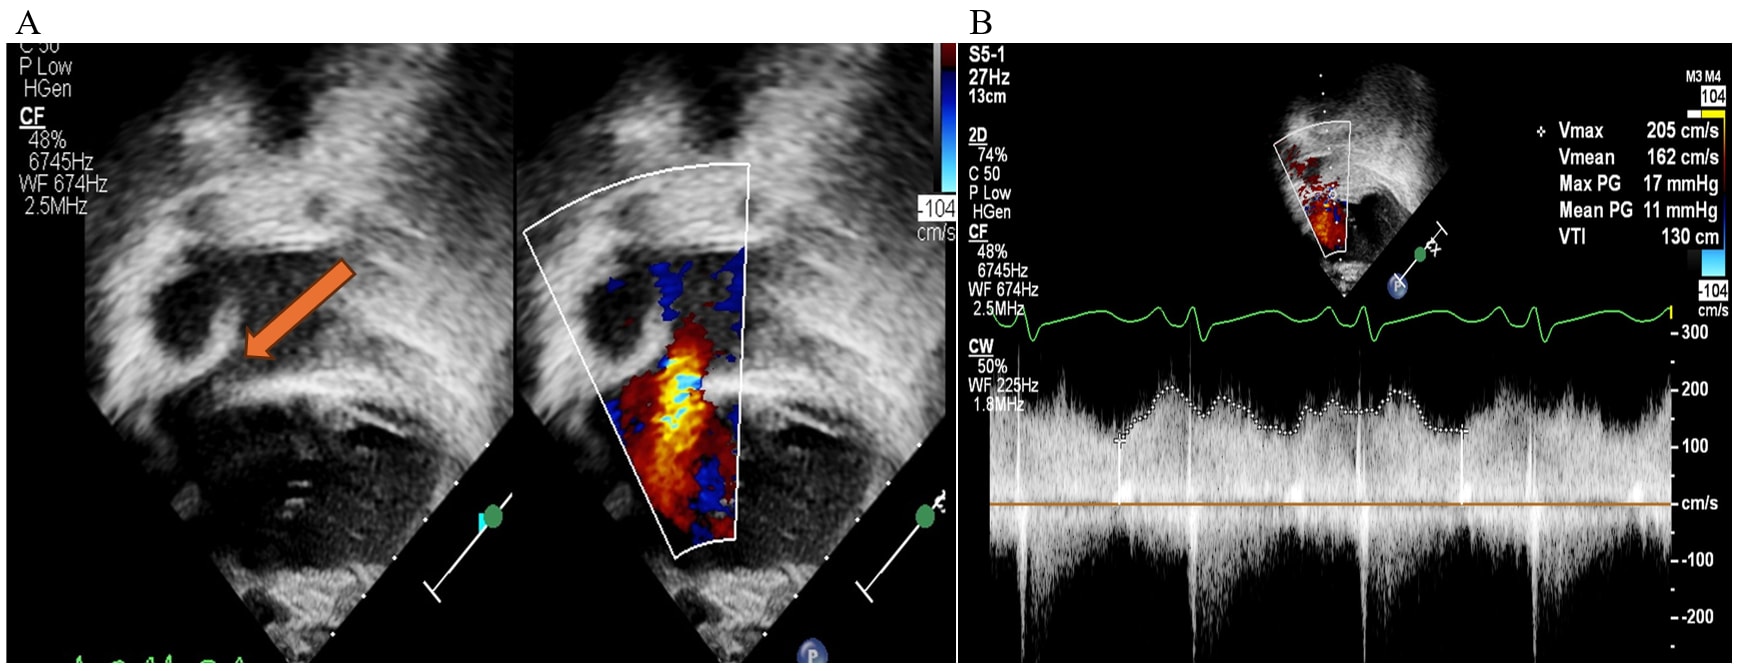

Surgical Systemic Vein Turndown For Thoracic Duct Decompression in Fontan Patients With Protein-Losing Enteropathy: Role of Multimodality Imaging

A recent American College of Cardiology expert analysis reviews surgical systemic vein (innominate vein) turndown as a promising treatment for protein?losing enteropathy (PLE) in patients with Fontan circulation.